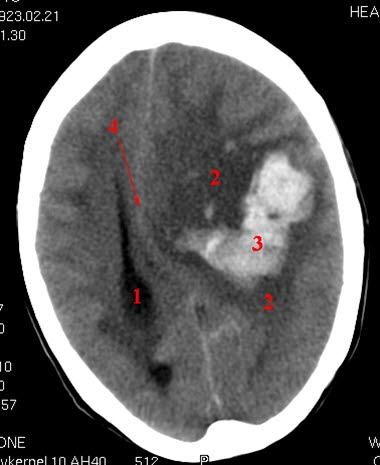

CT axialbilde uten kontrast

Blødning (lyst område) i hjernen på pasientens venstre side.

Betydelig ødem (mørkt område) rundt hematomet.

Venstre sideventrikkel er komprimert og midtlinjestrukturene er skjøvet mot høyre side

- Høyre sideventrikkel

- Ødemsone

- Blødning

- Midtlinjestrukturer